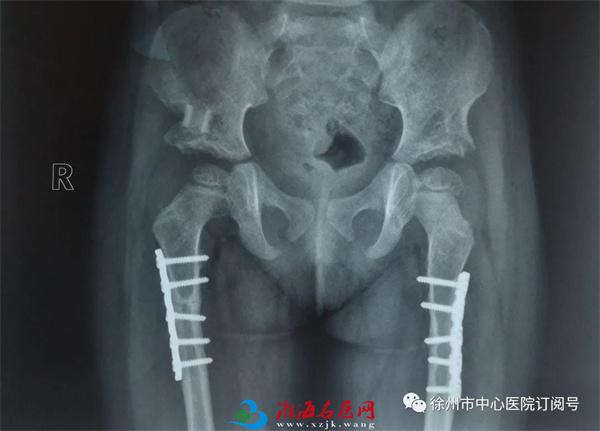

12年前,被查出患有严重双侧髋关节先天性脱位的4岁女孩小月在我院骨创伤外科接受了由黄建华主任医师团队实施的“髋臼周围截骨术+股骨短缩旋转截骨术”,12年后,前来复诊的她行走已与常人无异,并对黄建华表达了由衷的感谢。

由于患儿年龄小,皮肤娇嫩,身体尚在发育,这对手术医生的技术要求比较高。凭借多年的临床经验,黄建华决定为小月实施“髋臼周围截骨术+股骨短缩旋转截骨术”。术后,小月恢复良好。

2011年7月术后影像

2011年12月影像

2012年1月影像

今年,家人再次带着小月再次来到我院复诊,16岁的她髋关节发育正常,活动、走路时姿态与常人无异。